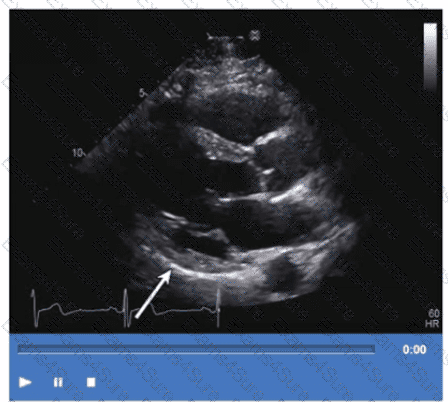

Which region of the aorta is being measured to assess the critical finding in this image?